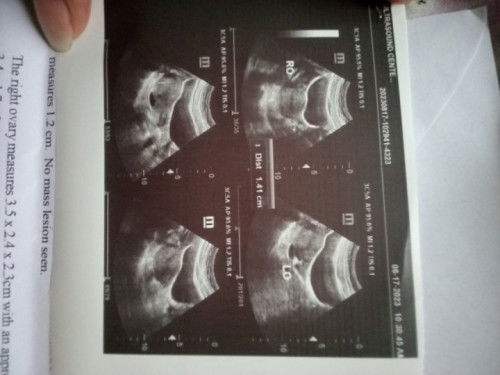

Hello mga mamsh may same case ba dito sakin na nagpa Transvaginal ultrasound tapos lumabas sa findings ni baby Fetal Tachycardia? 8 weeks and 4 days palang po sya na sstress kasi ako kung delikado poba ito or not. Nakita ko kasi sa google pwede mag cause ng heart failure magiging normal pa kaya ang heartbeat nya? Tyia #pregnant #Needadvice #mommy